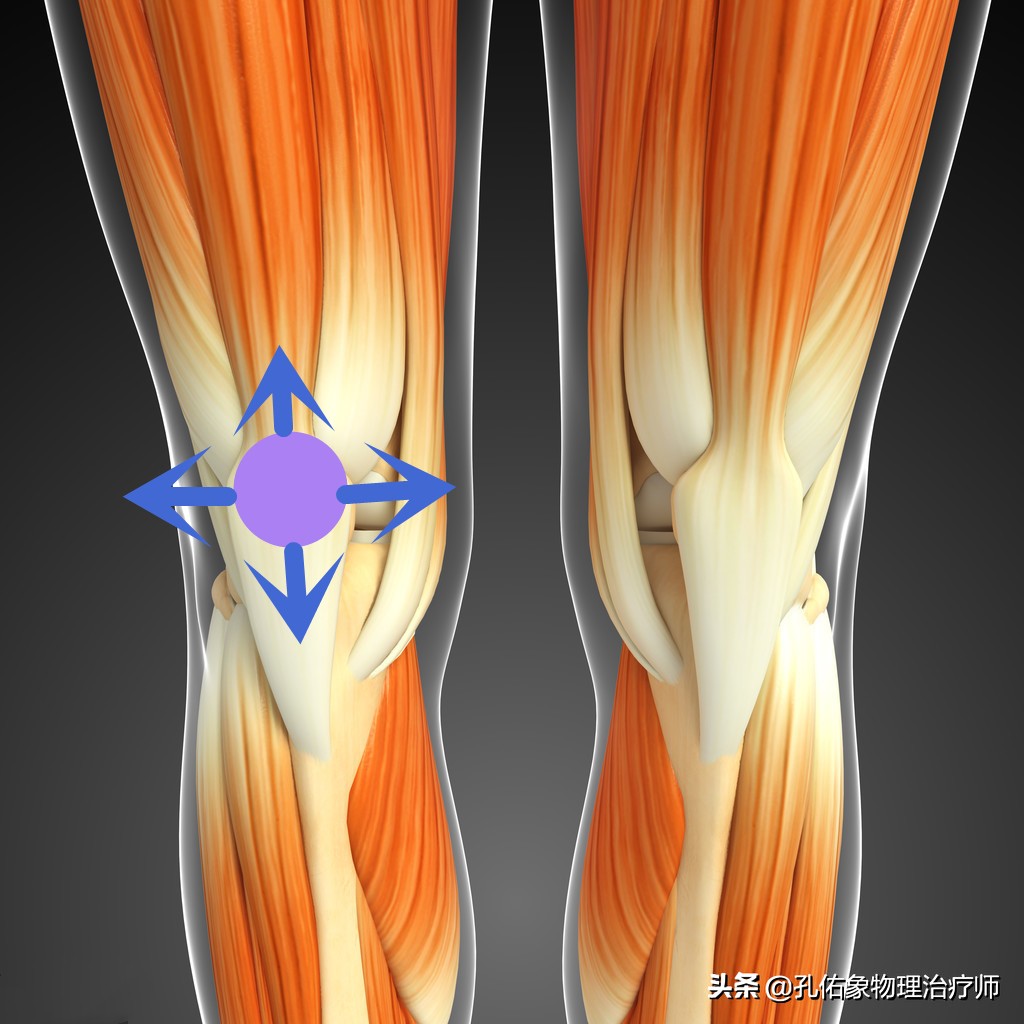

因为膝痛,会使稳定膝盖骨周围的韧带、肌肉打破原有的平衡;比方说现在很多人因不注意锻炼,常见于大腿外侧很紧,而膝盖骨内上缘处的股内侧斜肌就会很弱,从而影响到膝的受力,就会导致小腿发生旋转,最终使脚巴掌发生受力不均的情况下行走,毫无疑问就会出现足底疼痛。

检查时使膝盖骨与其相对应的大腿骨髁间关节面互相挤压研磨或上下左右的滑动,是否伴有粗糙的摩擦感、磨砂音和患肢膝关节的疼痛不适。

- 膝盖骨的活动度

完全把膝盖伸直,两拇指放在膝盖骨的外侧缘,向内侧推移膝盖骨。一般将膝盖骨的四分之一宽度定位1度。在正常的情况下,膝盖骨的内移程度在1-2度之间;若是超过2度,就说明膝盖骨的活动过大,小于1度就说明膝盖外侧的支持带紧张,即膝盖骨内移受限检查阳性。

第二步:该怎么治疗

到这里呢,治疗相对就很简单了,因为有前期的精准检查评估判断,你是哪里的肌肉软组织紧张?是哪里的肌肉软组织弱?导致膝盖骨的不稳定,偏移了正常的运动轨迹。只需要根据力学去强化和放松即可,当然理念方向找对了,治疗方法相对不固定,会很多的。

比如说,常见的大腿内侧斜肌和内收肌的离心力量强化训练,臀大肌的离心强化训练;阔筋膜张肌和髂胫束的放松训练;膝关节的本体感知训练等等。